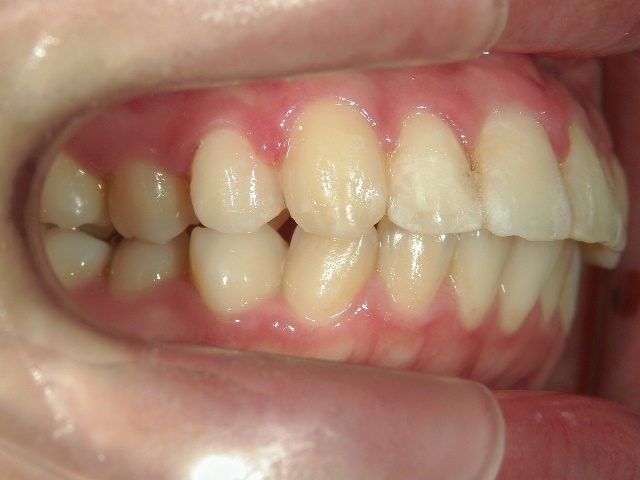

no.6_8296_治療前_右.jpgno.6_8296_治療前_正面.jpgno.6_8296_治療前_左.jpg

no.6_8296_治療後_右.jpgno.6_8296_治療後_正面.jpgno.6_8296_治療後_左.jpg